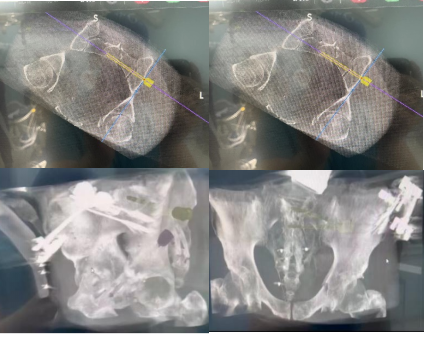

手术当天,骨科治疗组组长何罕亮副主任医师带领团队采用先进的二代臂机对患者进行骨盆图像采集,并将影像学资料上传至机器人计算机中。经过机器人的精密运算,患者的骨折三维图像非常直观地呈现在医生面前。随后,何主任团队根据图像实时进行手术规划,选择最佳置钉通道。手术机器人机械臂根据制定好的路线精准定位,将误差控制在1mm之内,使得医生不必扩大切口即可暴露骨折断端。只需3个毫米级切口,螺钉便可精准打入狭长的耻骨中,避免损伤重要的血管、神经组织。通道确定后,整个置钉过程短短几分钟便完成了,手术出血量不足10ml。精准的置钉操作使得医生不必担心反复调整所致的钉道松动,术后透视也进一步确认了螺钉位置准确无误,这预示着手术圆满成功。

机器人术中规划髋臼前柱螺钉&骨盆骶髂螺钉